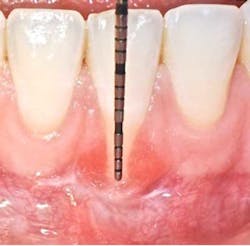

According to the proceedings from the 2014 American Academy of Periodontology Regeneration Workshop, root coverage may be attained through the application of a variety of surgical procedures. These outcomes are generally measured by reduced defect depth, gain in clinical attachment, and an increase in keratinized tissue. The associated systematic reviewprovides clear evidence that a subepithelial connective tissue graft (SCTG) procedure offers the best outcome for mean and complete root coverage, as well as an increase in keratinized tissue. (4,5) Strong evidence also supports biomaterials such as acelullar dermal matrix grafts (ADMG) or enamel matrix derivative (EMD) in conjunction with a coronally advanced flap (CAF) that can be used as an alternative to treat Miller Class I and II single-tooth gingival recession defects (figures 1 and 2). (6)Another suggestion from the proceedings was that using a split-thickness flap or tunnel technique can help to revascularize the graft by maintaining an excellent vascular supply to the flap.

There is certainly no panacea for treatment, but we have found this combination therapy provides our patients with long-term predictable, stable results. Our preferred treatment method for gingival recession defects affecting one to four teeth is to use a tunneling technique in combination with a subepithelial connective tissue graft, enamel matrix derivative, and a coronally advanced flap (figures 4-9). When treating four or more teeth, or if a patient is opposed to harvesting a SCTG, we use a tunneling procedure in conjunction with an acellular dermal matrix graft, enamel matrix derivative, and a coronally advanced flap.